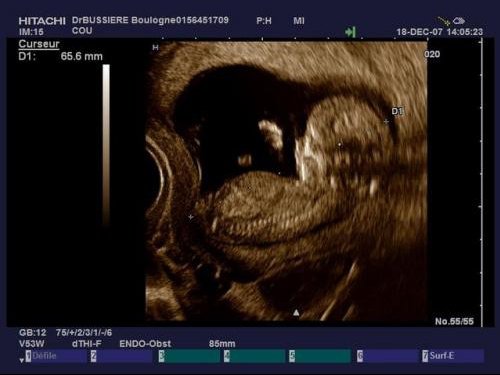

Battement coeur bebe fille garcon. Fille ou garçon. Mais je me surprends à chercher des indices là où il n y en a. Coucou j ai un petite question j ai entendu parler qu on pouvait savoir le sexe de bebe par rapport au battement de cœur par minute et qu ils faisaient comme ça dans le temps. Dans les temps anciens cette hypothèse avait une certaine part de probabilité car les gens remarquaient que dans le ventre de la mère le cœur des filles battait différemment du cœur des garçons.

Bonjour bb1 pour moi j ai eu une eco de datation avec 170 de battement de cœur par minute. Peut on vraiment savoir le sexe de bébé. Je ne sais pas si ca fonctionne réellement. Bien qu il n existe pas de test et de méthodes infaillibles certains signes pourraient vous mettre la puce à l oreille au fil des mois.

Battements du coeur. Selon vous filles ou garcon. Alors moi a 6 sa 3 son cœur battait a 127 bpm et a 8 sa 3 entre 160 et 180 bpm. Battement du cœur fille ou garcon.

Battement coeur foetus fille ou garcon. Deviner le sexe grâce au battement de cœur de bebe.